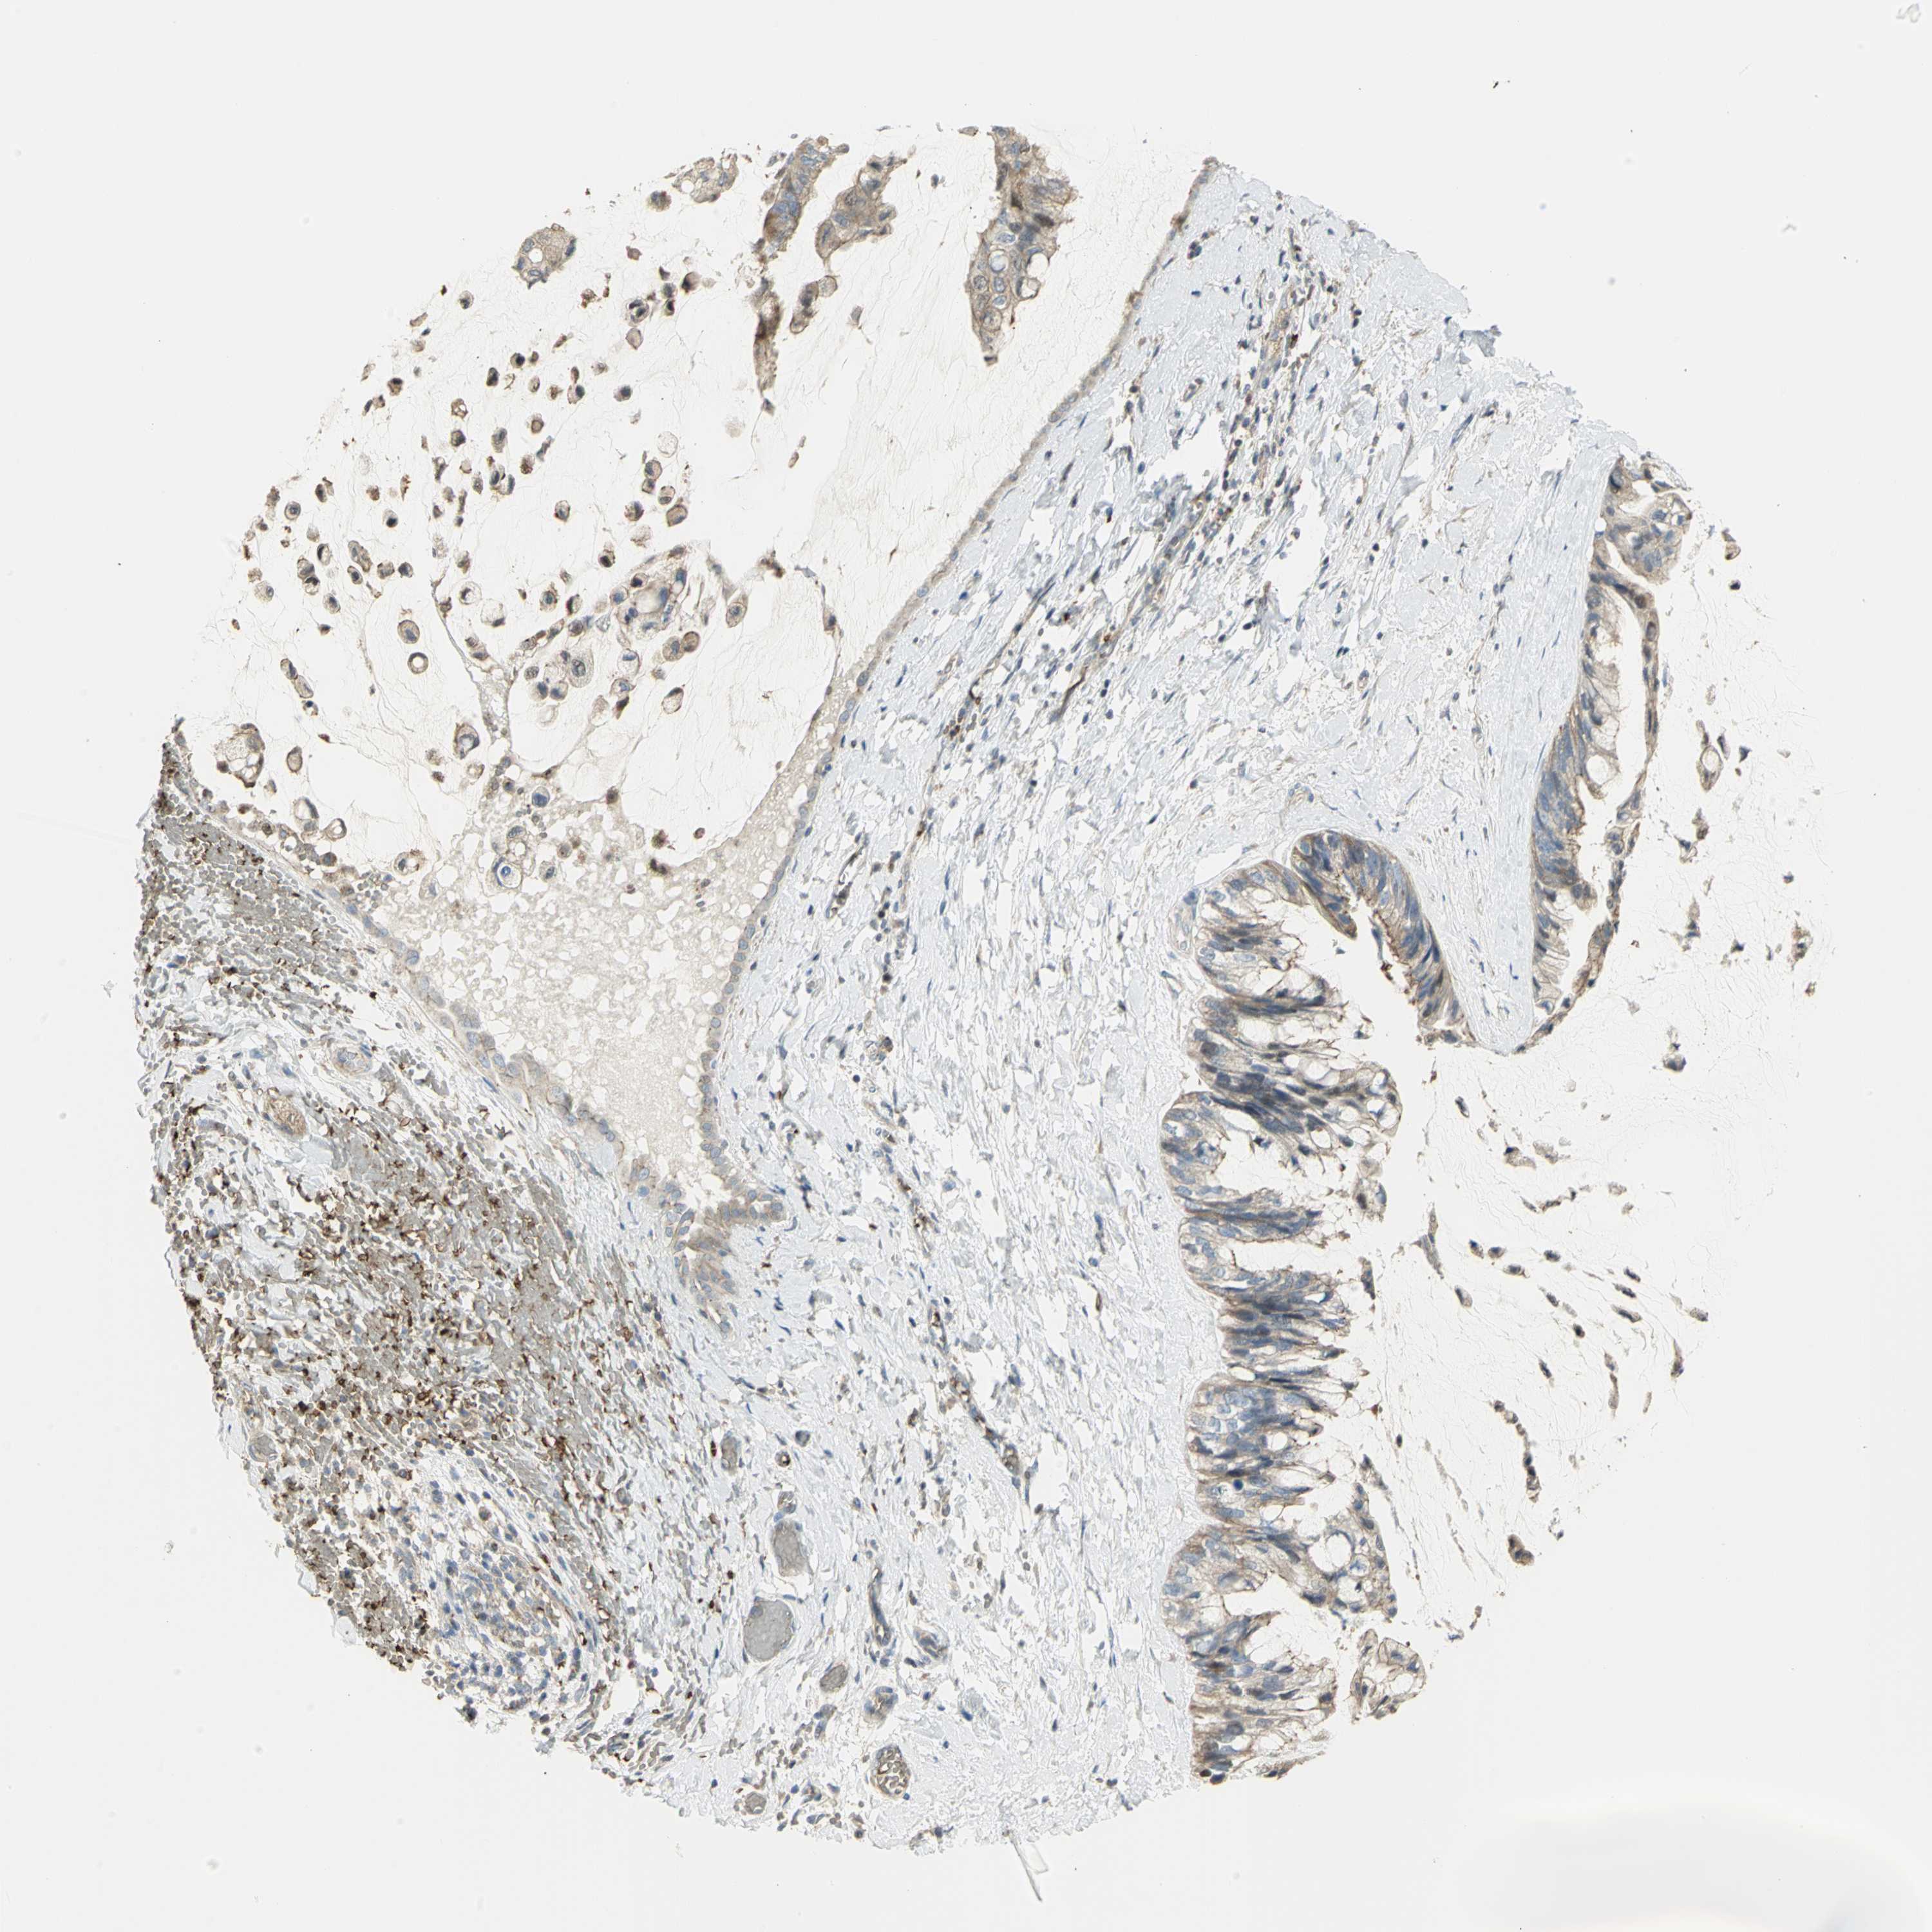

OVARIAN CANCER - Protein expressioni

A mouse-over function shows sample information and annotation data. Click on an image to view it in a full screen mode. Samples can be filtered based on level of antibody staining by selecting one or several of the following categories: high, medium, low and not detected. The assay and annotation is described here.

Note that samples used for immunohistochemistry by the Human Protein Atlas do not correspond to samples in the TCGA dataset.

Antibody stainingi

Antibody staining in the annotated cell types in the current human tissue is reported as not detected, low, medium, or high, based on conventional immunohistochemistry profiling in selected tissues. This score is based on the combination of the staining intensity and fraction of stained cells.

Each image is clickable and will lead to virtual microscopy that enables deeper exploration of all samples and also displays staining intensity scores, fraction scores and subcellular localization as well as patient and tissue information for each sample.

Antibody HPA004842

Antibody HPA056953

Cystadenocarcinoma, serous, NOS

Carcinoma, endometroid

Carcinoma, NOS

Cystadenocarcinoma, mucinous, NOS